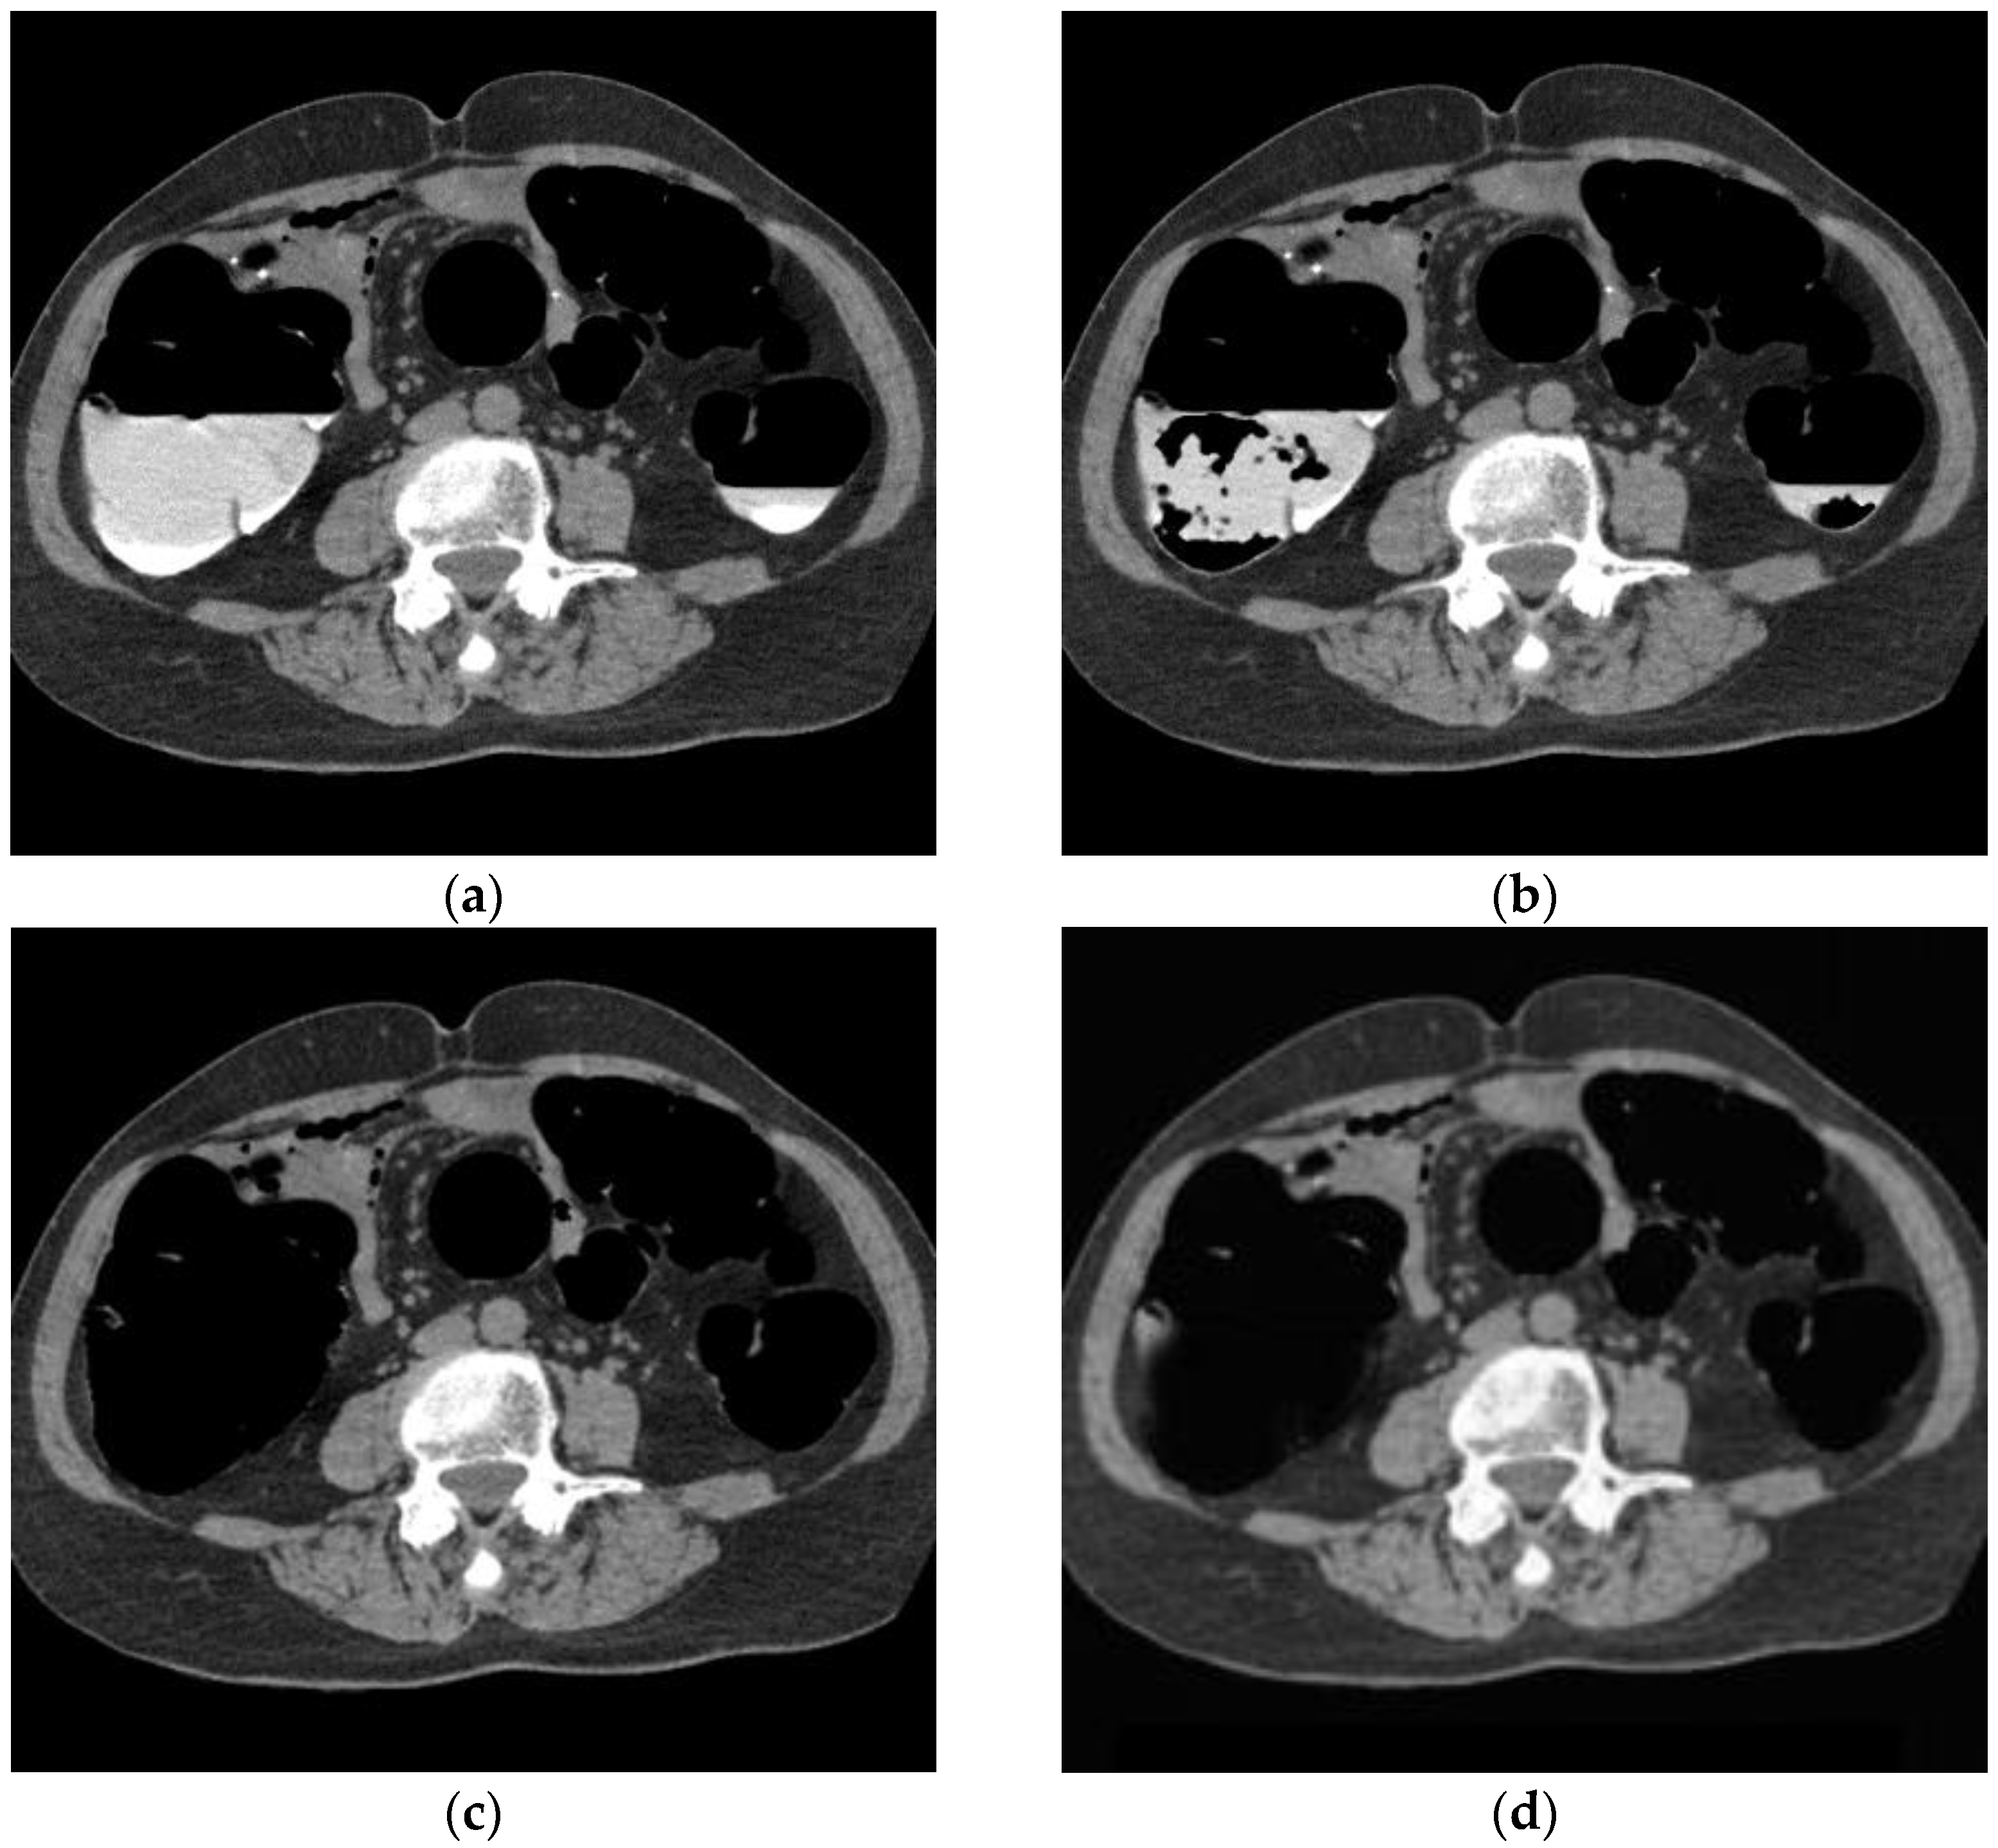

3.1. Cleansing Images Generated Using CycleGAN

4.1. Images Generated by CycleGAN